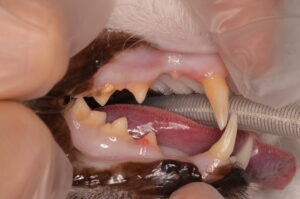

上の写真は今回の猫ちゃんの歯です。歯肉が赤く盛り上がり歯に覆いかぶさっているように見える部分がありますが、これが典型的な吸収病巣の見た目です。歯肉が覆っている部分の下の歯の表面が溶けていることが多いです。

よく「食べたそうにしても食べない」と相談を受けることが多いです。現在のところ、この病気を根治させる治療は確立されておらず、抜歯もしくは溶けている歯冠部(表に見えている部分)を切断することで痛みを取り除く治療が選択されます。今回の猫ちゃんも吸収病巣が痛みの原因と考えられたため、全身麻酔下で詳細な検査と抜歯を行うことになりました。